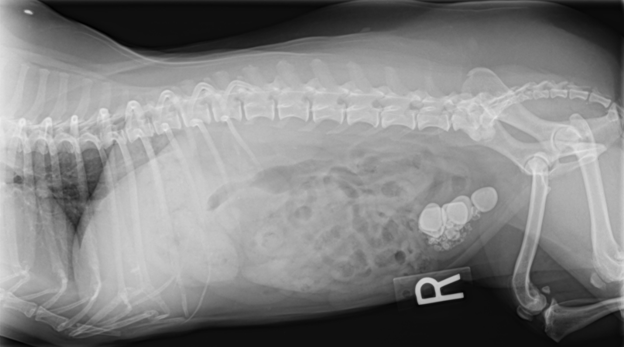

The type of diagnostic tests performed, depends on the animal’s age and general health. An abdominal ultrasound and/or abdominal radiographs may be performed to determine the specific problem within bladder and to evaluate other body systems. Typically, a general chemistry panel, complete blood count and electrolytes are conducted to evaluate your pet for any underlying problems prior to receiving anesthesia. A urinalysis will also be performed to evaluate kidney function and if there is an underlying urinary tract infection.